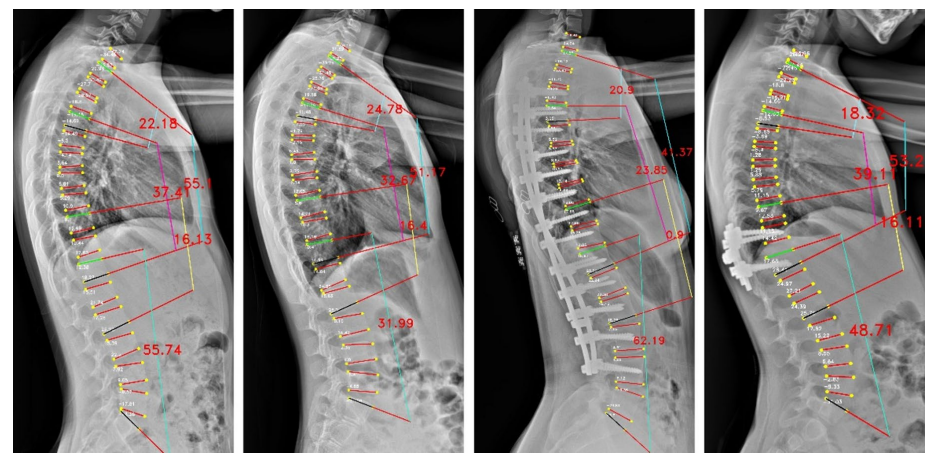

Cobb角是评估脊柱侧弯程度的"金标准",其测量结果可以用于评估病情、制定治疗计划和跟踪疾病进展。万东Cobb角自动测量系统,1秒内即可完成Cobb角计算,较传统手工测量(耗时>2 分钟)效率提升百倍。经研究验证,Cobb角平均测量误差仅3.918°,ICC为0.943,验证了该算法技术指标顶尖、误差小、重复性极好,相关论文收录于脊柱外科和脊柱研究领域的国际顶级期刊之一《European Spine Journal》。

The Pearson correlation only on major Cobb angle of AP view images

The vertebrae four corner points and the Cobb angles measurement for AP view images

The vertebrae four corner points and the Cobb angles measurement for LAT view images

基于负重位CBCT的全脊柱三维Cobb角自动测量,实现了椎体的高精度自动分割,其Dice系数达0.9776(自动分割的结果越准确,Dice值就越接近1),误差极小;三维Cobb角测量可接受度>97.05%,关键椎体识别准确率98.53%,显著优于传统方法。基于负重位CBCT椎体轴向旋转角度自动测量,与人工测量一致性ICC 达0.76,误差控制在±3.04° 内,实现了对椎体旋转的客观、高效、可重复测量,一键自动生成,高效助力临床精准诊疗。该研究入选中华医学会放射学学术大会(CCR 2025)。